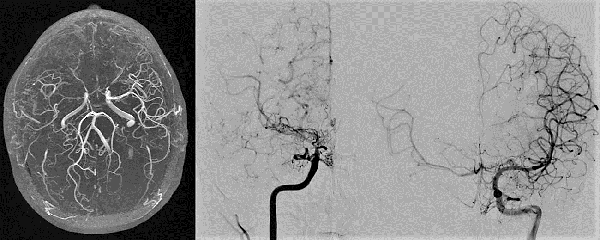

Caso clínico #3 (cirugía bilateral): GM femenino de 27 años, con antecedente de hipotiroidismo secundario a Enfermedad de Hashimoto; consultó por cuadro de parestesias y paresia leve braquial izquierda de más de 6 meses de evolución. La RMN evidencia pequeñas imágenes isquémicas en ambos centros semiovales a predominio derecho; la ARM y ADC muestran la estenosis severa de ambas arterias carótidas internas y ausencia del origen de ambas arterias silvianas con vasos de MM presentes; corresponde a un grado 3 de Suzuki (Fig. 6). Se realizó primero un bpTS derecho más EDMS y, a los 10 meses, otro bpTS más EDMS izquierdo con buena evolución en ambas revascularizaciones. La ADC alejada muestra franca mejoría de la perfusión cerebral bilateral más marcado a la izquierda (Fig. 7 y 8).

Fig. 6 Caso clínico #3. Preoperatorio. A la izquierda, la RMN evidencia pequeñas imágenes isquémicas en ambos centros semiovales mayor a derecha, la ADC muestran la estenosis severa de ambas arterias carótidas internas supraclinoidea y ausencia del origen de ambas arterias silvianas, vasos de MM presentes correspondiente a un grado 3 de Suzuki

Fig. 7 Caso clínico #3. Postoperatorio. ADC lado derecho que muestra buena perfusión cerebral del bpTS (las flechas rojas muestran el curso de la aTS) y la EMDS

Fig. 8 Caso clínico #3. Postoperatorio. ADC lado izquierdo con muy buena perfusión cerebral desde el bpTS (las flechas rojas muestran el curso de la aTS) y la EMDS